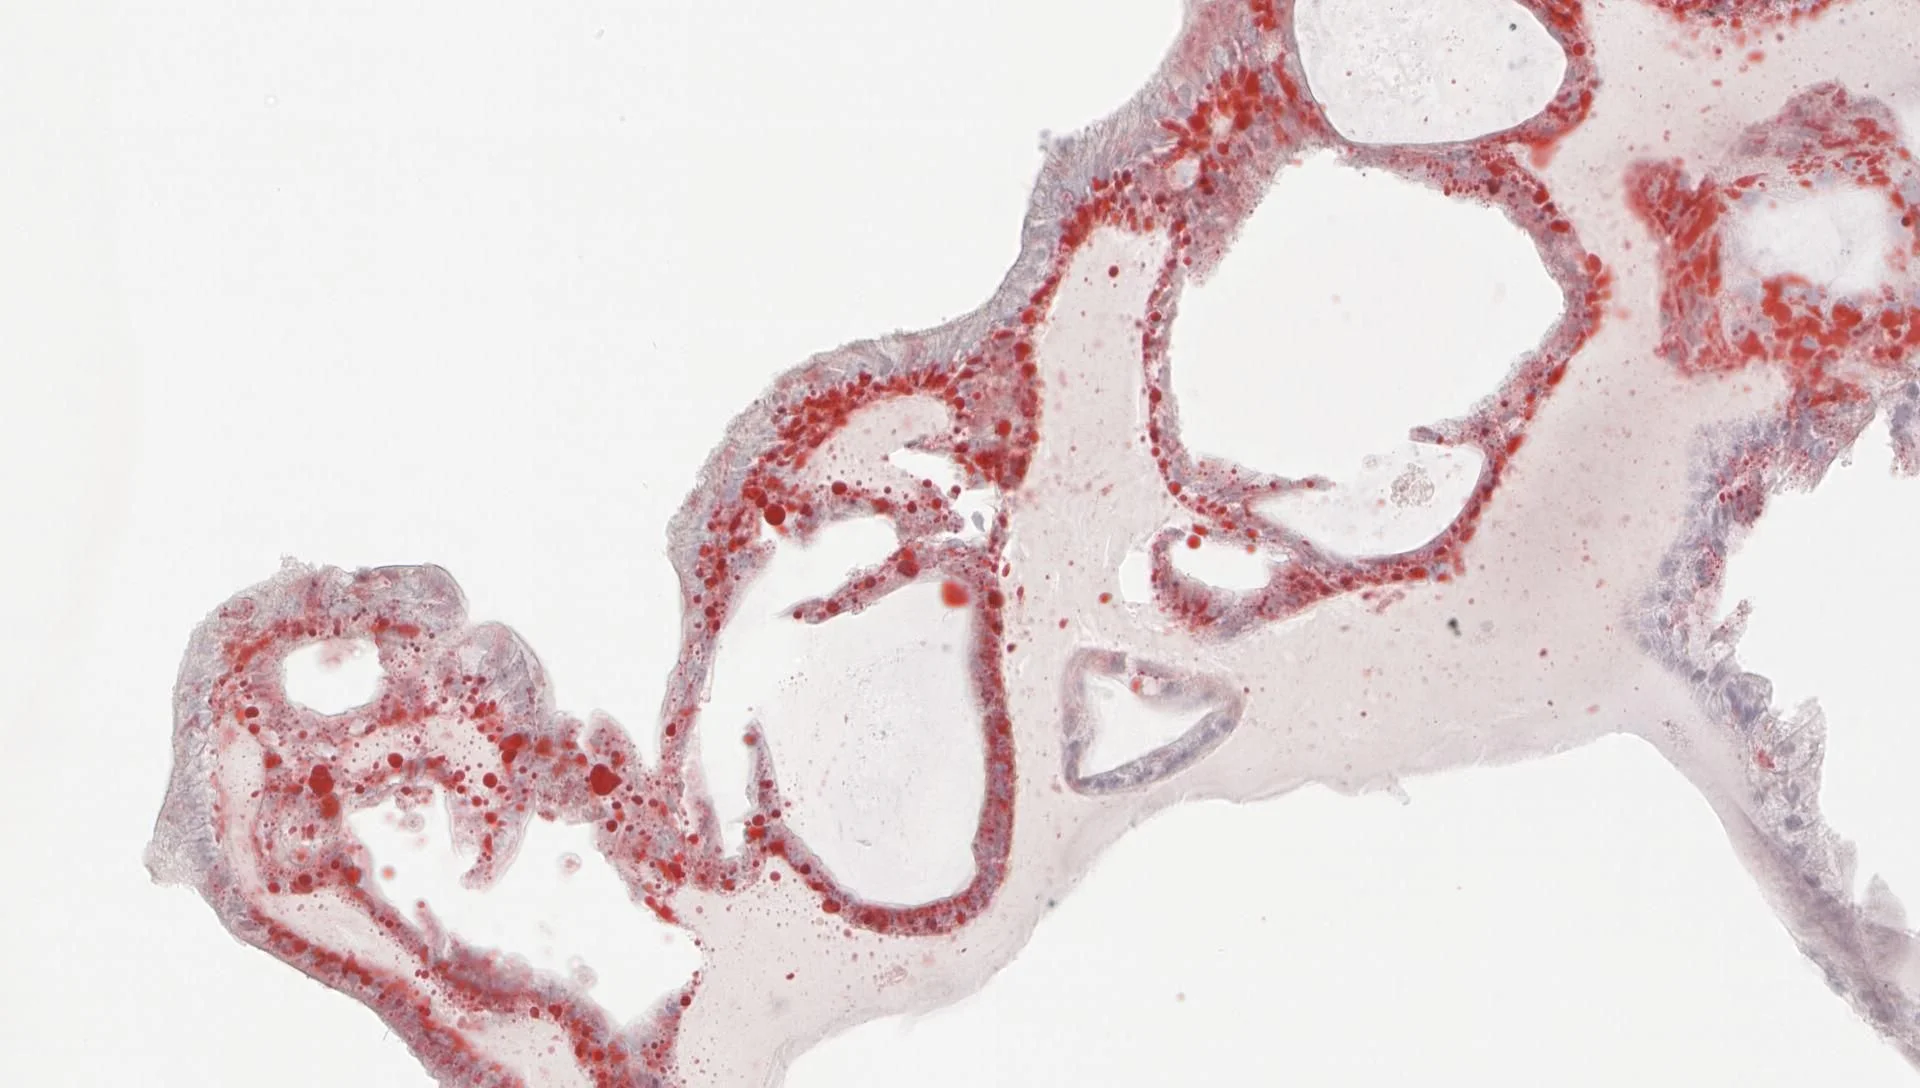

This work is a strong reminder of just how critical high-quality, experienced histology is to maximising the value of research using precious human samples. Our Westmead Histology Facility team, led by Li Ma, has been working closely with a researcher from the Storr Liver Unit at The Westmead Institute for Medical Research to optimise an Oil Red O staining protocol for hepatocyte organoid sections. Careful protocol optimisation like this ensures lipid-containing vacuoles are visualised clearly and consistently, protecting the integrity of downstream analysis and interpretation.

When working with human-derived samples, there is little room for error. Skilled histology transforms limited, irreplaceable material into reliable, information-rich data, making the difference between a sample being merely used and its full scientific value being realised.

Oil Red O is widely applied across biomedical research, including:

- marking lipid-containing vacuoles

- staining liver sections for histological analysis

- quantifying cellular lipid content

- examining aortic lesions associated with atherosclerosis

Images are kindly provided by Dr Romario Nguyen, Storr Liver Unit.